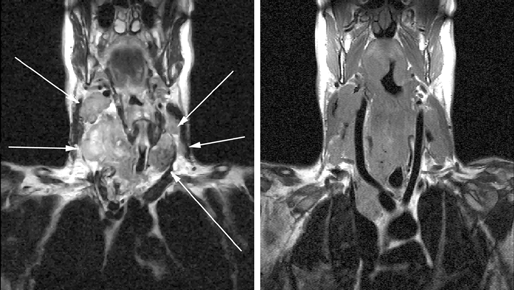

Исследования, проведенные нами в последние годы у 65 больных раком щитовидной железы, показали, что применение РКТ в сочетании с МРТ позволяет в высоком проценте случаев до операции иметь информацию о взаимоотношении распространенной опухоли щитовидной железы с окружающими анатомическими структурами (рис. 3, 4, 5).

Рисунок 3. МРТ: опухолевое поражение обеих долей щитовидной железы, метастазы в лимфатические узлы шеи с обеих сторон и средостение